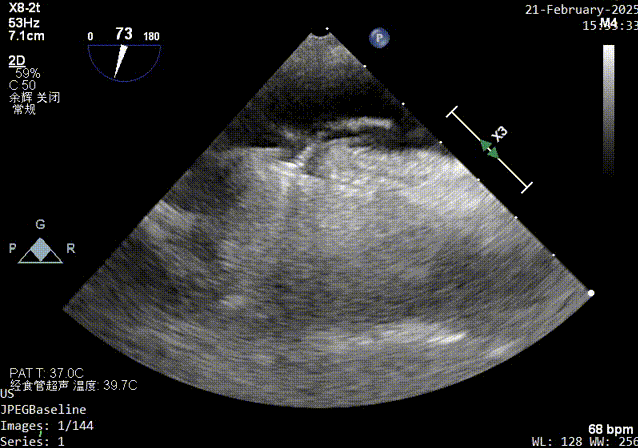

原发隔缝合超声影像

锁结器锁结操作时超声影像

锁结器锁结操作后超声影像